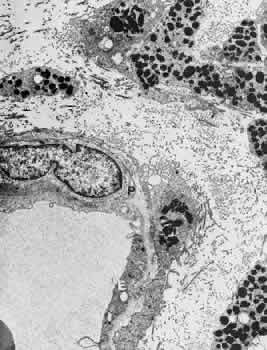

Retinal arterioles are similar to the arteries except that the lumen is small (8 to 15 μm in diameter), the media contains one or two layers of circularly or obliquely arranged smooth muscle cells, and the adventitia is poorly developed and consists of the outermost layer of basement membrane surrounding the smooth muscle cells and small amounts of collagen fibrils (Fig. 4).15

Fig. 4. Electron micrograph of a human retinal arteriole from the nerve fiber layer. This specimen was treated with ruthenium red. E, endothelial cell; S, smooth muscle cell; L, lumen; V, vitreous.